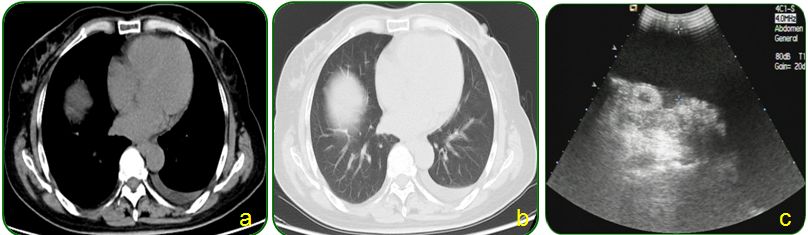

肺部CT提示双肺纹理增多、左侧胸腔少量积液,如图7a-b;

腹部彩超示腹腔积液,如图7c。

图7 胸部CT及腹部彩超检查

常规胸片检查提示胸腔积液,因此进一步行肺部CT检查,提示肺部CT提示双肺纹理增多、左侧胸腔少量积液,似乎本例和例2非常相似,同时胸腹腔积液。完善了腹部彩超、肝炎病毒学和PPD试验等检查,初步排除了肝硬化和结核菌感染,也未发现肿瘤征象。那么到底是什么原因呢?